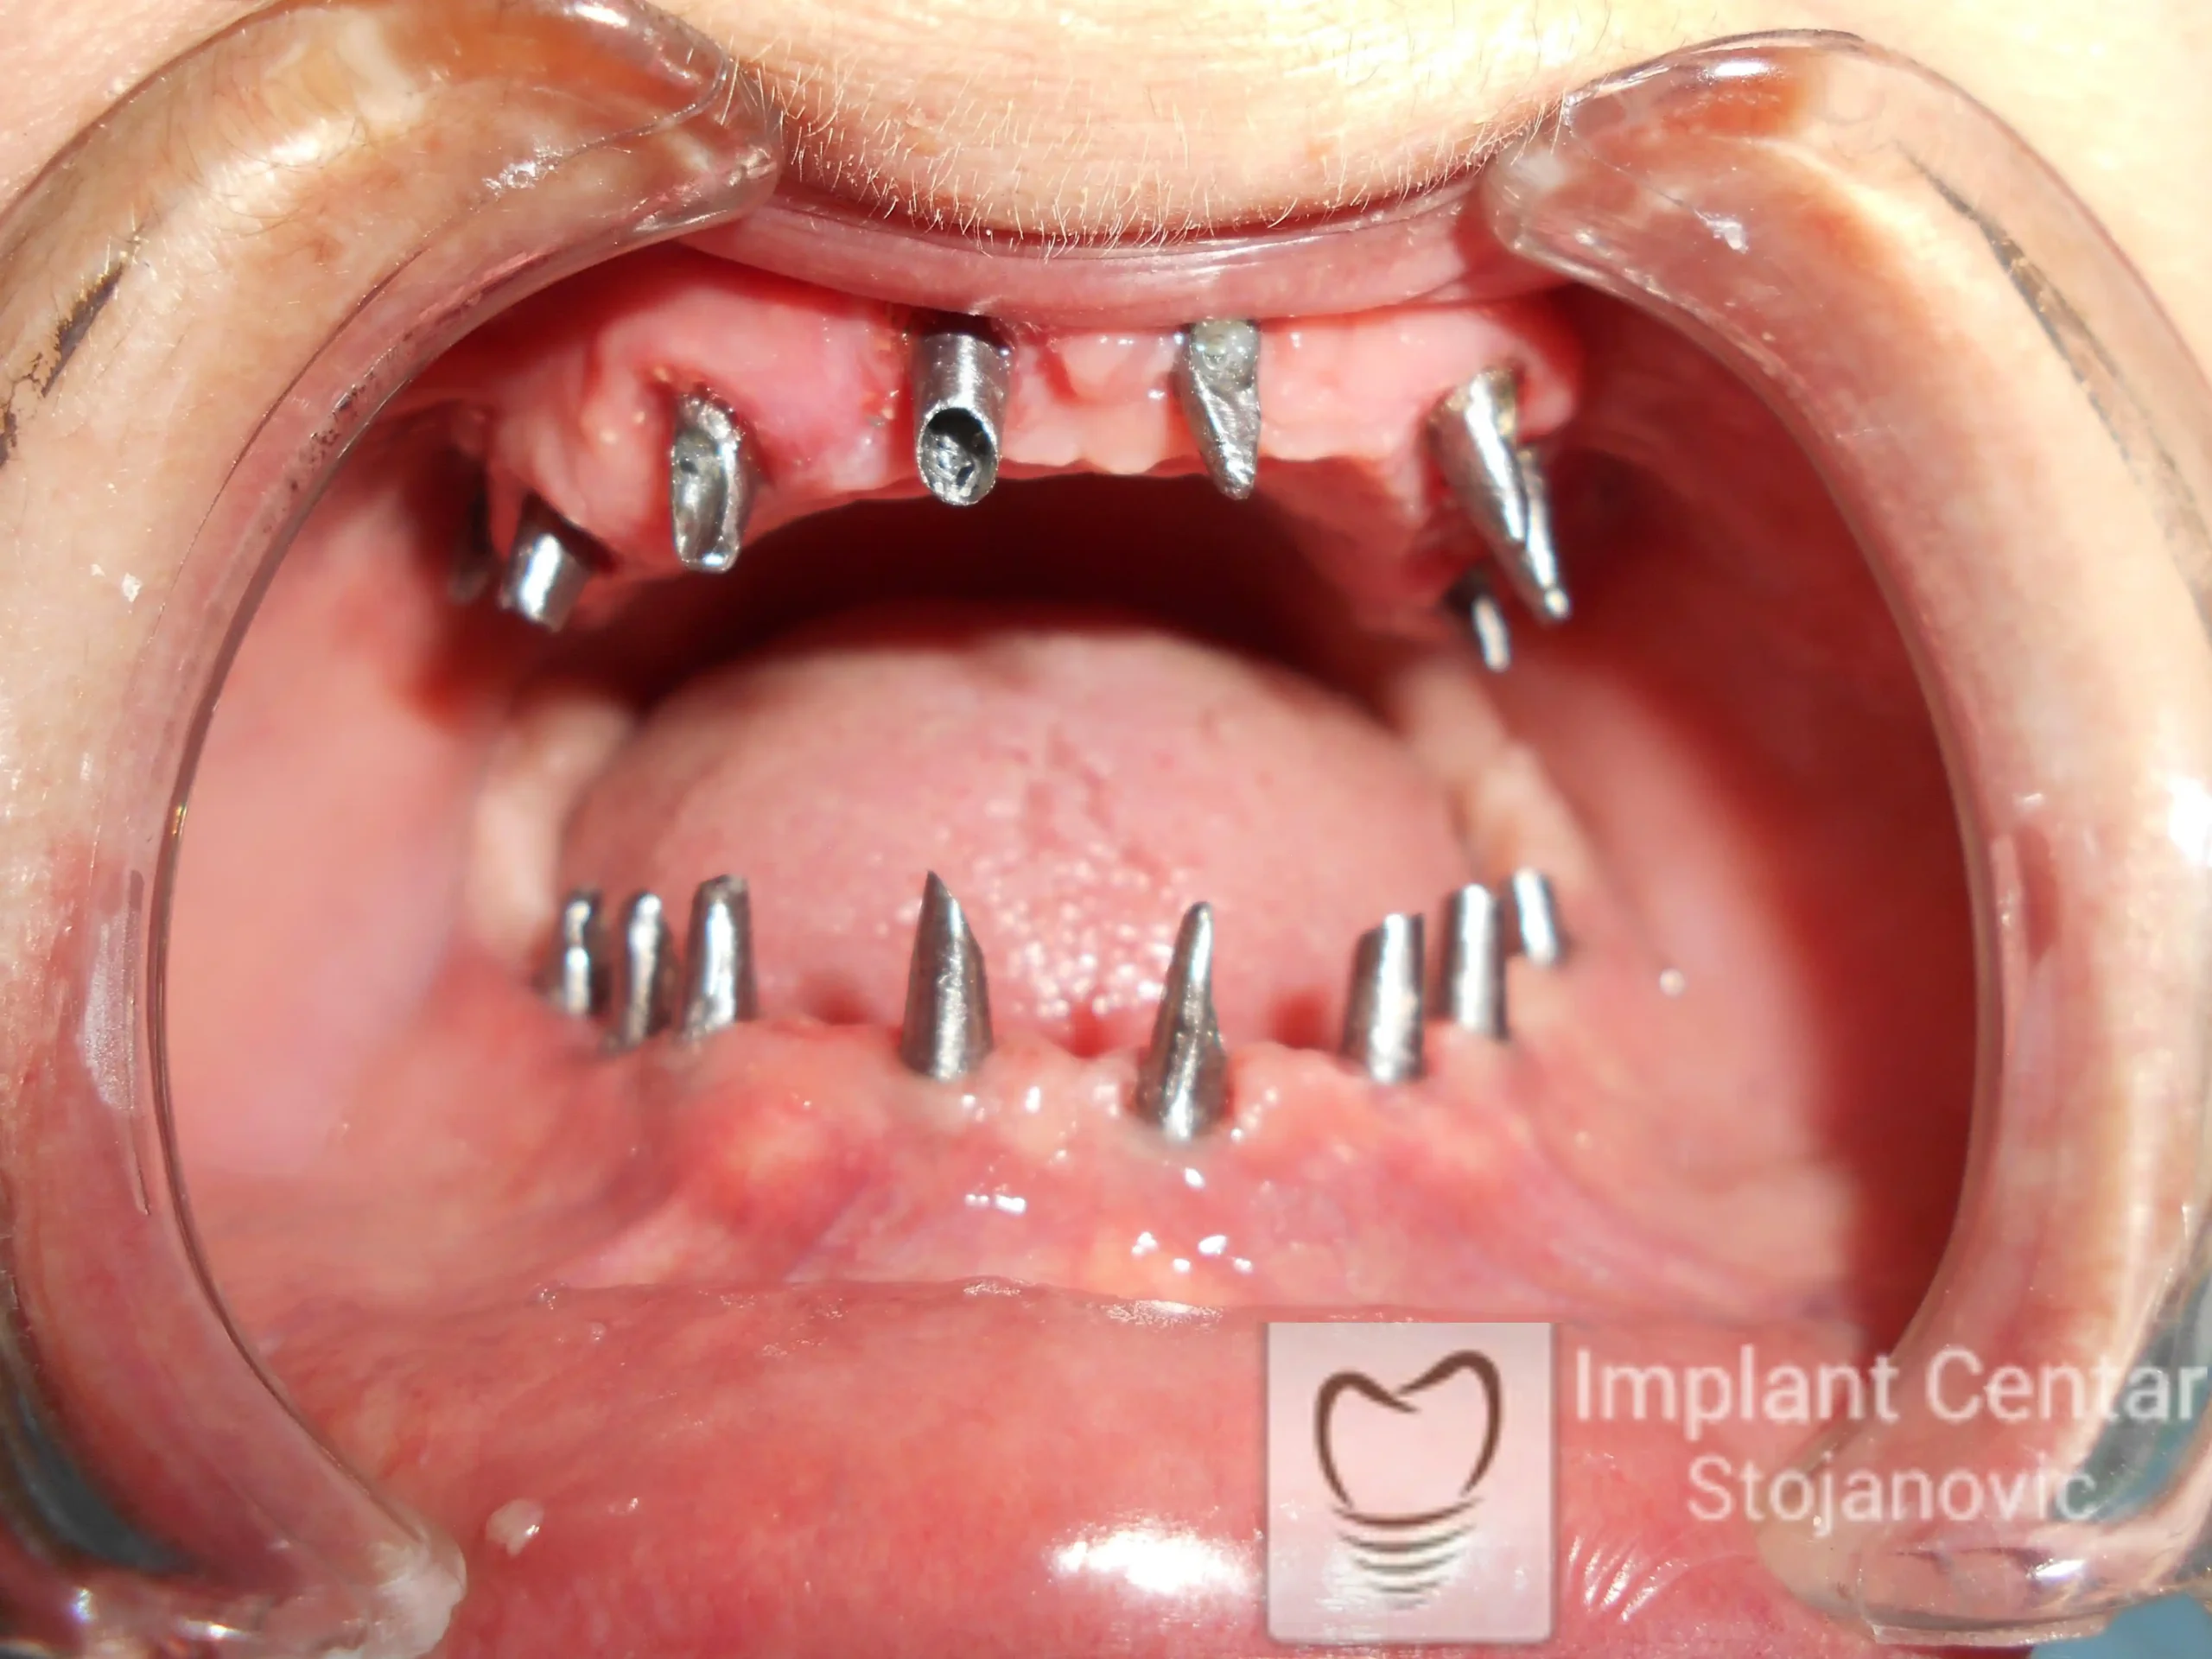

Pacijent sa rascepom usne, nepca i alveolarnog grebena uspešno je rehabilitovan fiksnim protetskim radom na implantatima. Pre dolaska u našu ordinaciju, pacijent je u gornjoj vilici nosio totalnu protezu preko preostalih zuba, dok je u donjoj vilici bio zbrinut parcijalnom mobilnom protezom. Tokom višegodišnje potrage za adekvatnim rešenjem, pacijent nije uspeo da pronađe zadovoljavajuću terapijsku opciju ni u zemlji ni u inostranstvu.

Nakon detaljnog kliničkog pregleda i analize radioloških snimaka, izrađen je sveobuhvatan plan terapije sa ciljem uklanjanja mobilnih proteza i postizanja maksimalne funkcionalne i estetske rehabilitacije. Zbog loše biološke vrednosti preostalih zuba, doneta je odluka o njihovom vađenju i ugradnji dentalnih implantata.

Poseban terapijski izazov predstavljalo je premošćavanje defekta nastalog usled rascepa, kao i ograničena količina raspoložive kosti u gornjoj vilici. Primenom većeg broja implantata i odgovarajućih procedura nadoknade kosti, postignuta je stabilna osnova za fiksni protetski rad.

Tokom perioda oseointegracije, pacijent je bio zbrinut fiksnim privremenim krunicama, čime je već pet dana nakon intervencije obezbeđena potpuna funkcionalna i estetska rehabilitacija. Nakon završetka perioda integracije implantata, izrađeni su definitivni cirkonijum-keramički mostovi na implantatima.